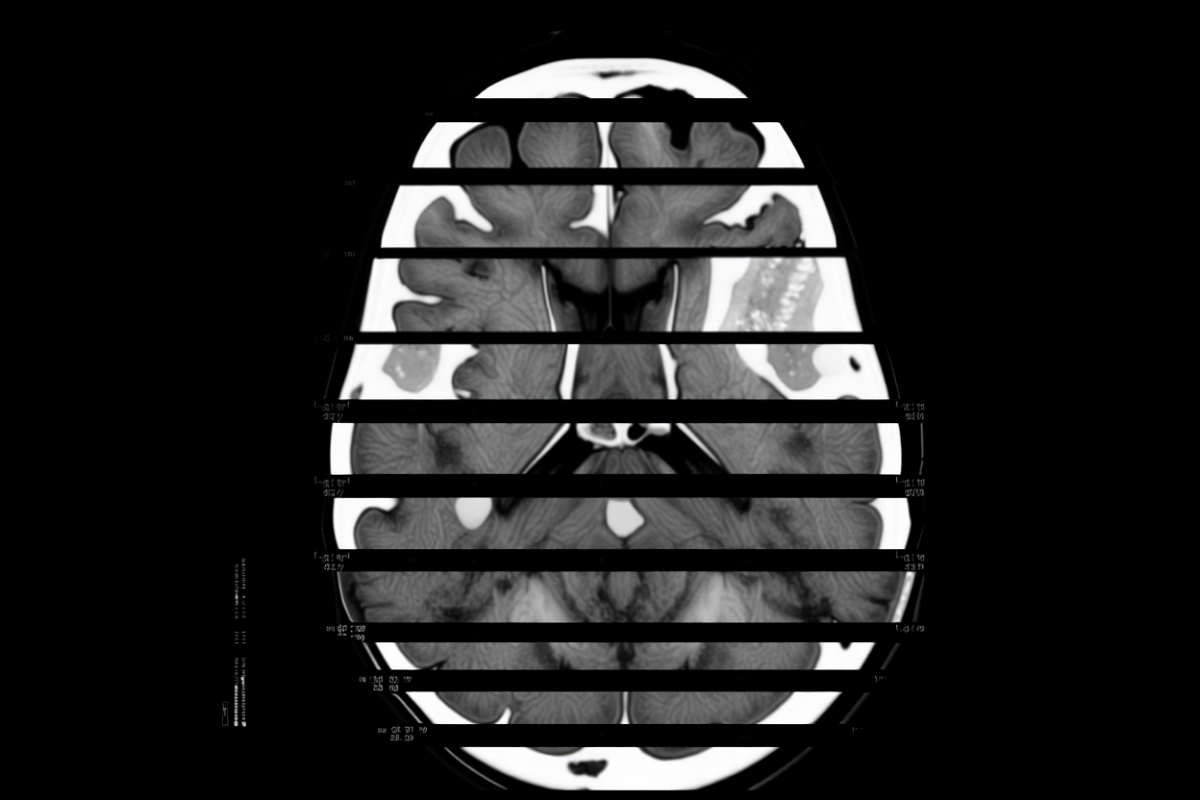

сгенерировано ИИ, источник: shedevrum.ai

С 2021 года компания внедряет медицинскую платформу, а в 2024 году получила регистрационное удостоверение Министерства здравоохранения РФ на собственное программное обеспечение, признанное медицинским изделием. Система искусственного интеллекта используется для анализа КТ-снимков мозга и уже внедрена в 12 регионах страны.

Текущая версия ИИ успешно определяет признаки инсульта и рассеянного склероза. По словам Паламарчука, на финальной стадии готовности находится модуль, позволяющий выявлять деменцию и болезнь Альцгеймера на раннем этапе.